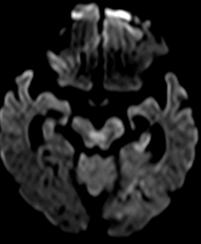

2例目を紹介いたします。81歳女性、自宅にて意識がなく、倒れているところを発見されました。来院時、JCS200と重篤な意識障害、左共同偏視、右片麻痺を認めました。頭部MRIにて脳幹に淡い梗塞、(図1)MRAにて脳底動脈の閉塞を認めました。(図2)再開通しなければ、死亡率が高い病態です。緊急にて血管撮影を行い、脳底動脈の閉塞を認めました。(図3)Penumbra吸引カテーテルと血栓除去用ステント(Trevo provue 4×20mm)を用いて血栓除去を行い、TICI3の完全再開通を認めました。(図4)翌日のMRIでは脳幹に梗塞を認めるも、(図5)意識障害は急速に改善しました。超高齢なために、約2ヶ月間のリハビリテーションを経て自宅へ戻りました。

![]() 図1:MRI拡散強調画 一部脳幹に淡い虚血を認めます。 |